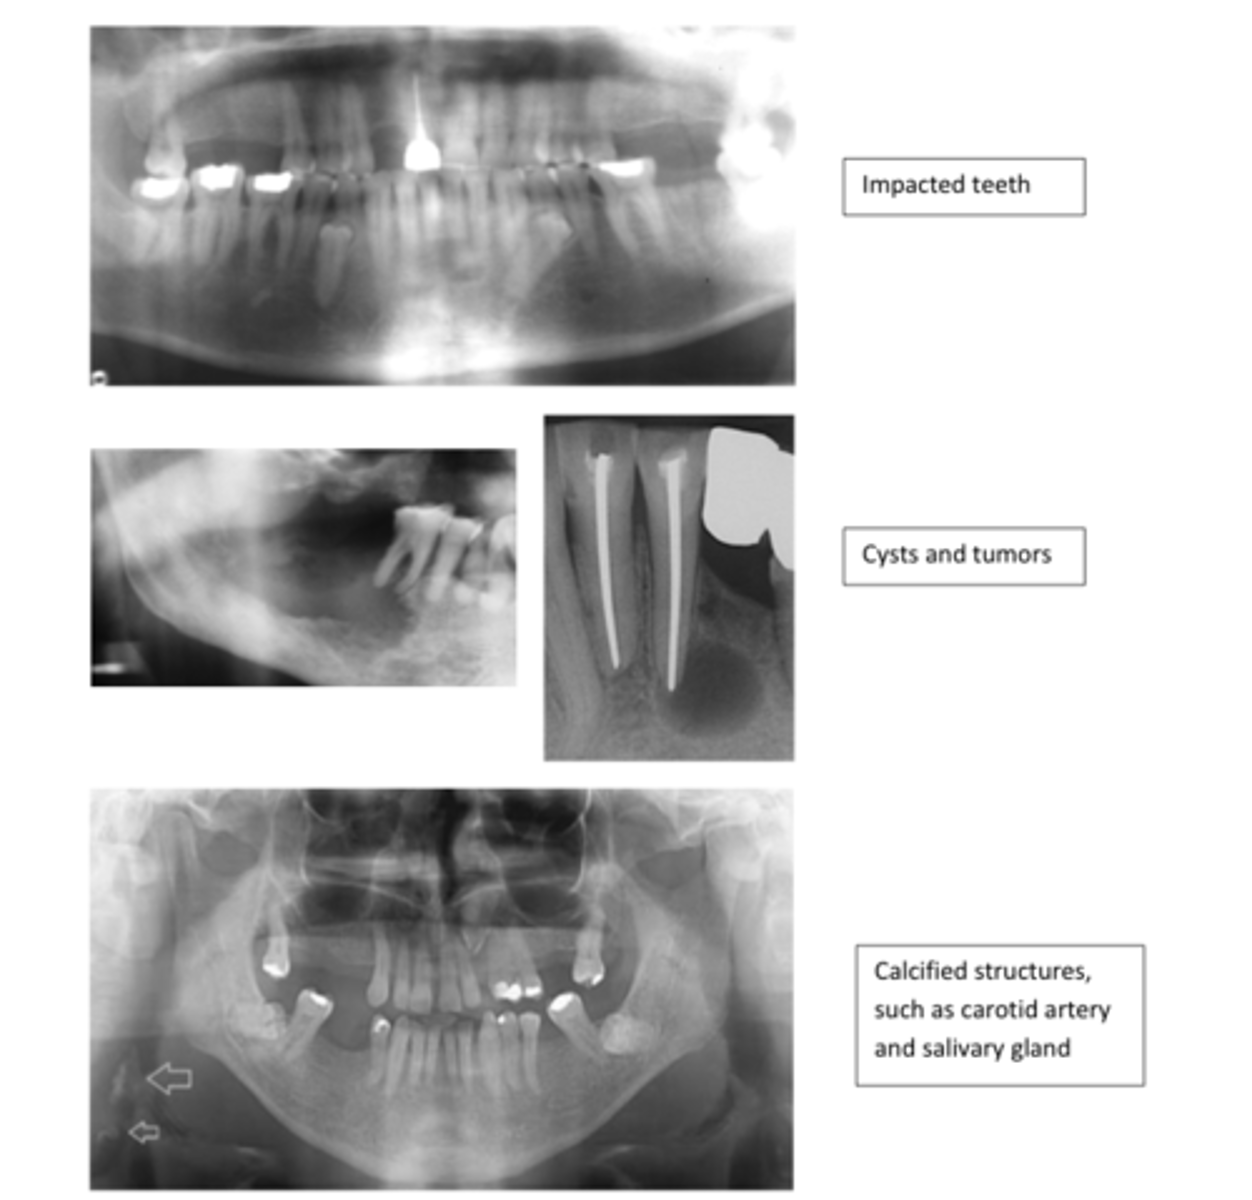

Permits the transmission of X-rays

Appears black:

- composite resin

- procelain

Any substance that blocks the transmission of x-rays

Appears white:

- silver amalgam

- gold

- CaOH

- pins & posts

- Gutta percha

- SSC

- implants

4 Types of Radiographs:

BW

PA

Panoramic

Occlusal